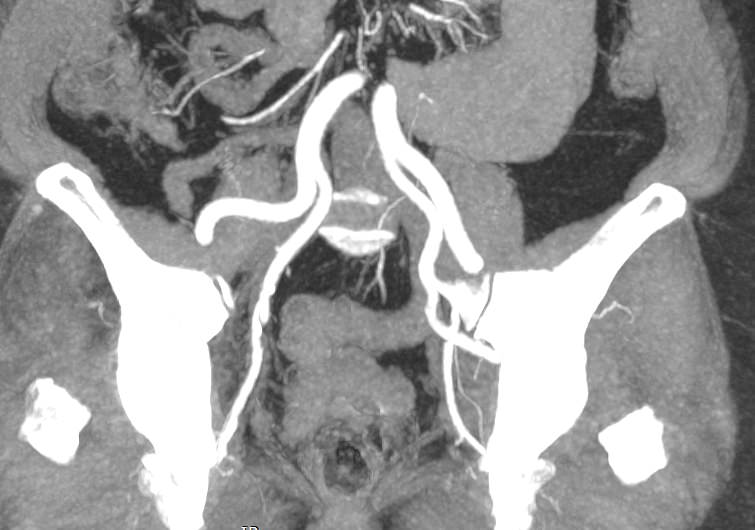

При нативной КТ кровеносные сосуды не видны. Поэтому, чтобы детально визуализировать сосудистую систему, обязательно проводится контрастное усиление. Для этого в периферическую вену пациенту вводится контрастный препарат, который попадая в кровеносное русло, поглощает рентгеновские лучи и ярко контрастирует сосудистую систему малого таза. В результате получаются детализированные снимки кровоснабжения внутренних половых органов, мочевого пузыря, прямой кишки.

На снимках КТ-ангиографии с контрастированием четко видна брюшная аорта, место ее разветвления на подвздошные артерии (бифуркация), а также сосудистые ветви, отходящие к органам малого таза. Снимки и 3D-изображения позволяют оценить: